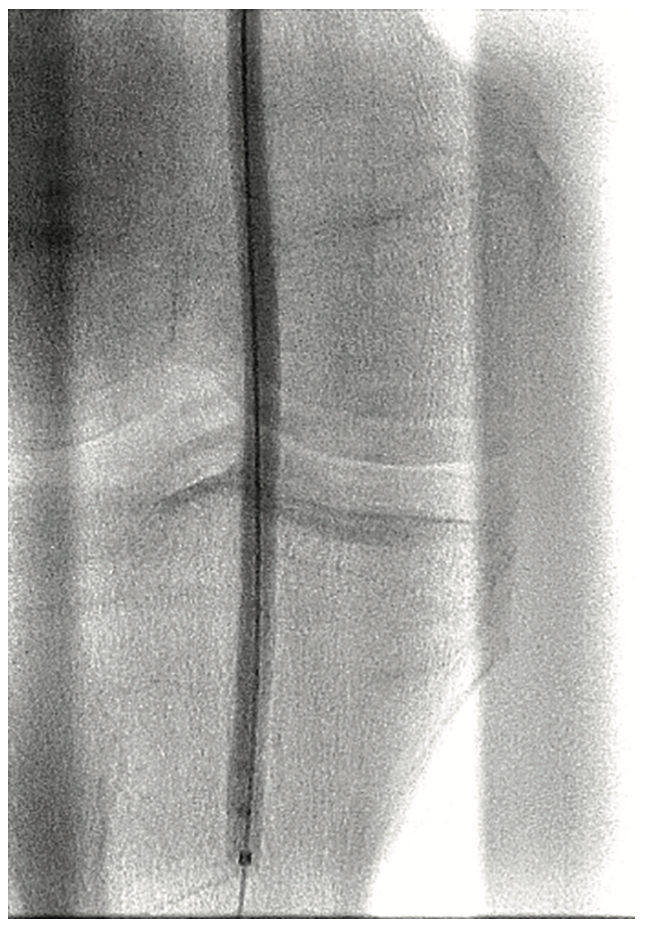

A 6 French (Fr) sheath was inserted into the right femoral artery in an antegrade fashion. An .035-inch x 90 cm Trailblazer (Medtronic) was inserted over an .035-inch x 180 cm Aquatrack guidewire (Cordis, A Cardinal Health company) and advanced into the right popliteal artery. Angiography was performed prior to surgical cut down of the posterior tibial artery (PT) (Figure 1). Access into the PT was made using a 4 Fr micropuncture pedal sheath (Cook Medical). An .014-inch Confianza guidewire (Asahi Intecc) was inserted and advanced into the PT. Using the stiff Confianza, a Viance Flexible CTO catheter (Medtronic) was advanced. When Viance extravasated from the PT, an Aquatrack wire and .035-inch Trailblazer were introduced and advanced in a antegrade manner. The Viance and Trailblazer could be visualized going in different directions (Figure 2). Using that image, the Viance was pulled back and repositioned to find the true lumen from the bottom to the top, using the guidance from the wire. The Confianza was readvanced after the true lumen was found, and Aquatrack was pulled back into the Trailblazer and eventually removed. The Confianza wire was advanced further into the .035-inch Trailblazer, and eventually pulled through the right femoral artery sheath in a retrograde fashion (Figure 3). The right femoral artery Trailblazer was removed. A TurboHawk SX-C atherectomy catheter (Medtronic) was used to debulk the plaque and achieve luminal gain from the popliteal artery into the tibioperoneal trunk (Figure 4). Drug-coated balloon angioplasty was performed using the IN.PACT balloon (Medtronic) into the popliteal artery (Figure 5). The TurboHawk was reinserted and advanced further down to the peroneal artery into the tibioperoneal trunk in order to establish luminal gain in the distal vessel. Final angiography revealed successful recanalization of the lower extremity vessels through the use of the antegrade/retrograde method, with distal access through the posterior tibial artery (Figure 6).